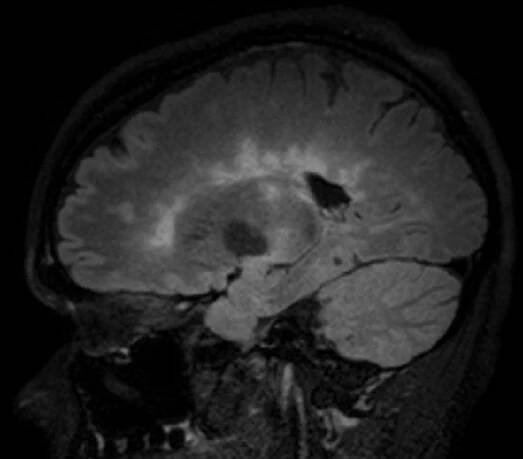

Vícečetná tumoriformní ložiska mozku jako první projev…

Tumoriformní demyelinizace patří mezi vzácné formy RS, její diferenciální dia¬gnostika může být obtížná, proto je nutno v první řadě vyloučit jiné dia¬gnózy, jako jsou např. mozkový tumor či absces.